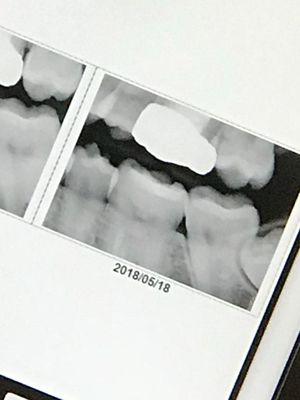

That is exactly how I was for about a year! Finally got them out about a year ago and migraines have subsided tremendously. Honestly if you have the time I’d go ahead and get them removed because its better to do it now than wait for them to abscess or something because that’s a common happening with impacted wisdom teeth it happened to my mom and almost to me.